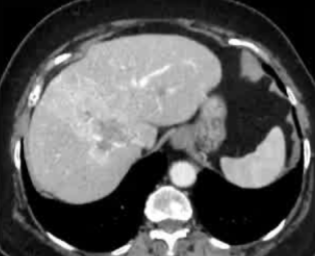

· 单中心、样本量小; 83 岁的女性,体重超标 40 毫米单发 ICC(S7-S8) 中肝静脉和右肝静脉浸润性,活检:非酒精性脂肪性肝炎(慢性肝病),马斯氏(MaS)病(30%)

考虑采用“三步策略 TARE→ PVE → Surgery”方案 剂量活性:1.56 和 3.16 GBq